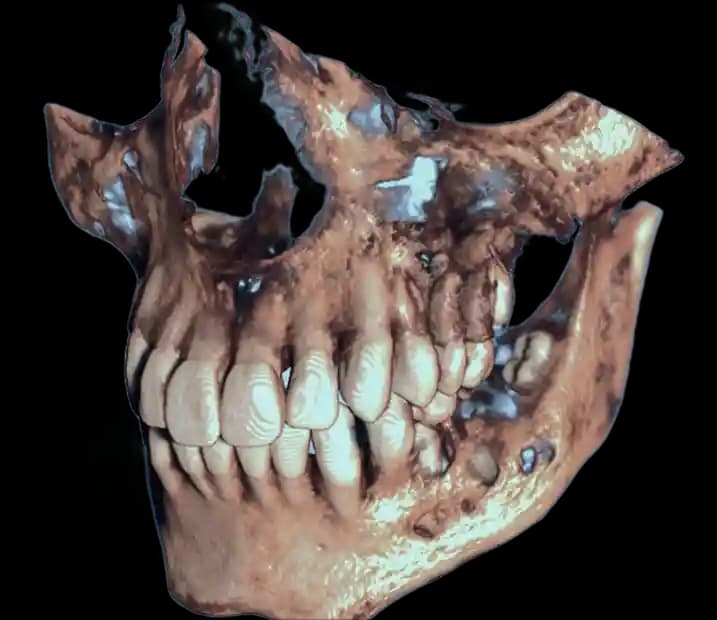

From routine 2D scans to complex 3D segmentations, get specialist-level interpretations tailored to your clinical needs.

High-precision DICOM conversion into 3D anatomical models and STL files ready for surgical guides.